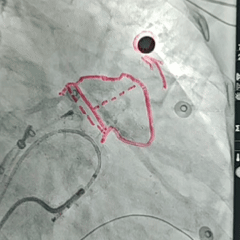

封堵器展开后造影

封堵器展开后肝位造影,封堵器完全封堵,无残余分流

牵拉试验

回弹明显,封堵器稳定锚定在心耳内部

测量压缩比

-

封堵器露肩4-5mm,在LAFDQ-29允许露肩范围内;

肩部压缩比为:8-11%,符合推荐压缩比8-30%,压缩合适。